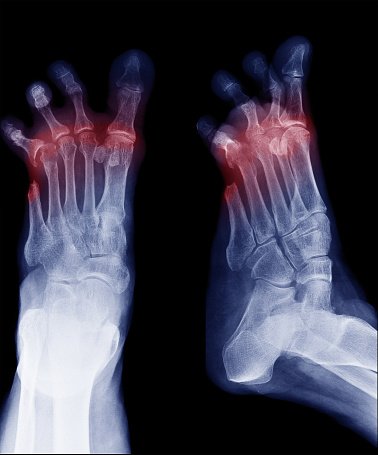

O estudo elaborado a partir de informações disponíveis na base de dados do Ministério da Saúde acende o alerta para os cuidados voltados às doenças vasculares, como a síndrome do pé diabético. De acordo com os especialistas, mais da metade dos casos de amputações envolvem pessoas com diabetes. No entanto, essas cirurgias em membros inferiores podem também estar relacionadas a muitos outros fatores de risco, como tabagismo, hipertensão arterial, dislipidemia, idade avançada, insuficiência renal crônica, estados de hipercoagulabilidade e histórico familiar.

O diabetes impacta a circulação sanguínea porque gera o estreitamento das artérias, causando redução dos índices de a oxigenação e nutrição dos tecidos. Além disso, deformações nos pés e alterações de sensibilidade aumentam a chance do surgimento de pequenos ferimentos e potencializam sua evolução para casos mais graves. “Estudos apontam que 85% das amputações que possuem relação com o diabetes têm início com uma lesão nos pés, que poderiam ser prevenidas ou tratadas corretamente evitando complicações”, destaca o presidente da SBACV.

Além desse contexto, a SBACV considera que o atraso no diagnóstico da síndrome do pé diabético faz com que o paciente seja encaminhado ao especialista apenas quando o problema já está em seu estágio mais avançado. Portadores da diabetes devem estar atentos aos cuidados relacionados ao controle do nível glicêmico no sangue e aos sintomas que podem ser observados em autoexames realizados diariamente.